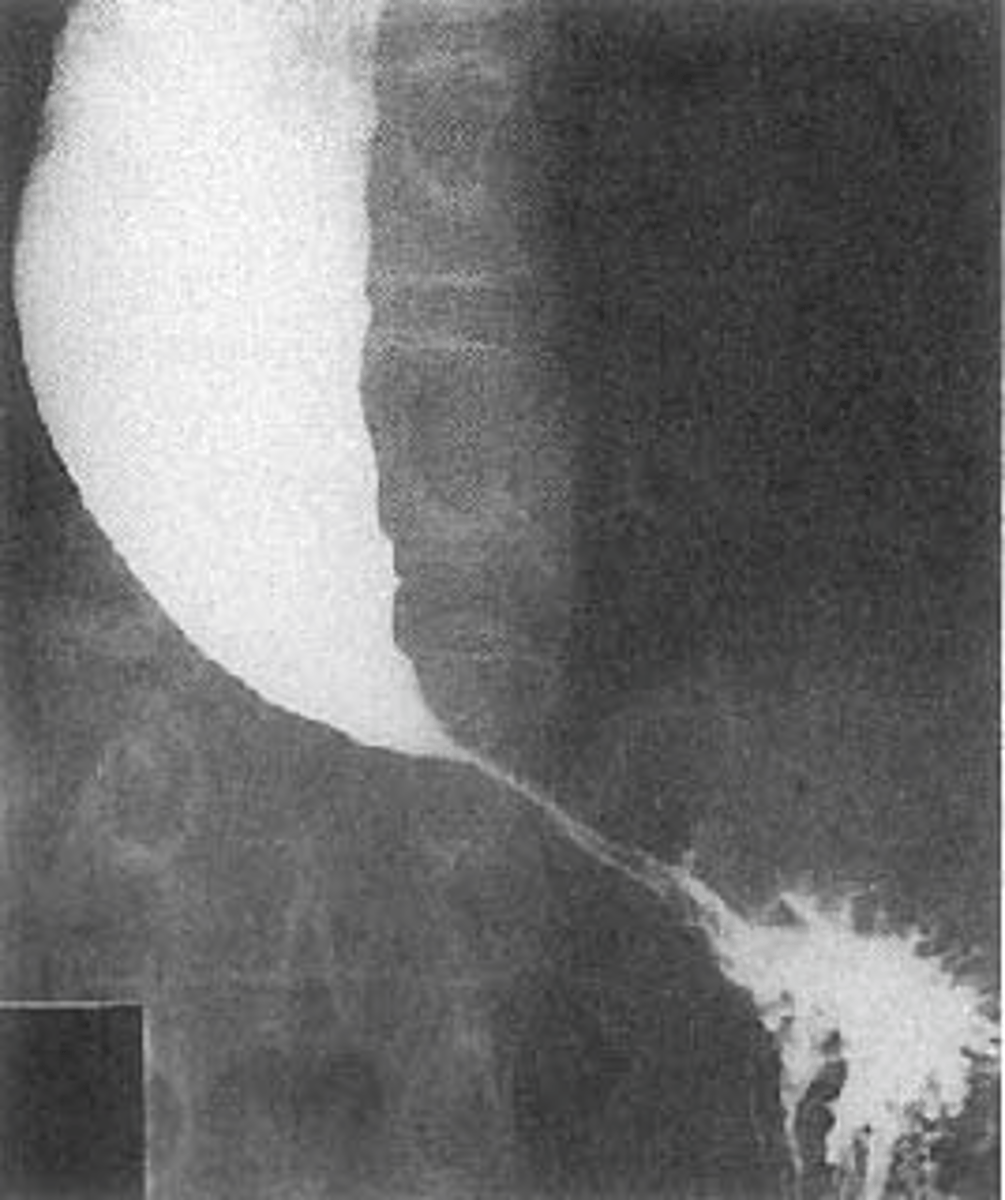

Upper left esophageal carcinoma

Lower left barrett's esophagus

Esophageal carcinomas.

(A)

DOTTED BLACK ARROW:

annular constricting lesion of the midesophagus.

The tumor encircles the normal lumen and obstructs it in this case.

(B)

BLACK ARROW: Polypoid mass that arises from the right lateral wall of the esophagus and displaces the barium around it.

(C)

BLACK ARROW - wall, irregular and rigid

WHITE ARROW: a small ulceration (white arrow).